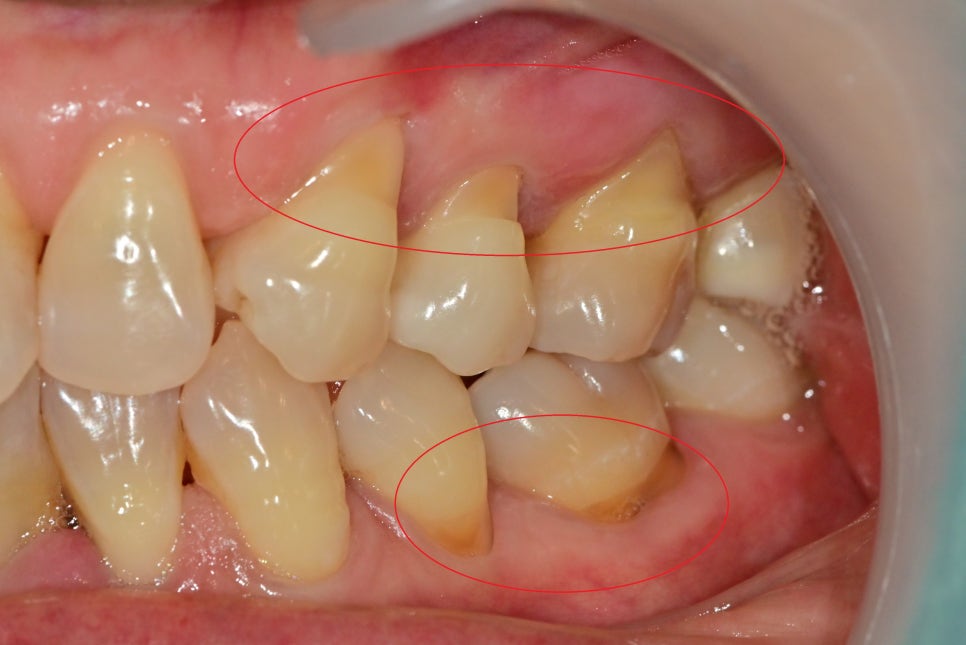

이런 경우는 치아의 교합력이 강하기 때문에 치아의 반복적인 파절이 자주 일어납니다.

대부분 이런 분들은 턱 부분의 교근이 상당히 강하게 발달이 되어 교합력이 강하게 발생하기 때문에

보톡스를 이용한 교근의 운동성을 줄여주게 되면 교합력의 감소로 이어져 치아 보존에 도움을 줍니다.